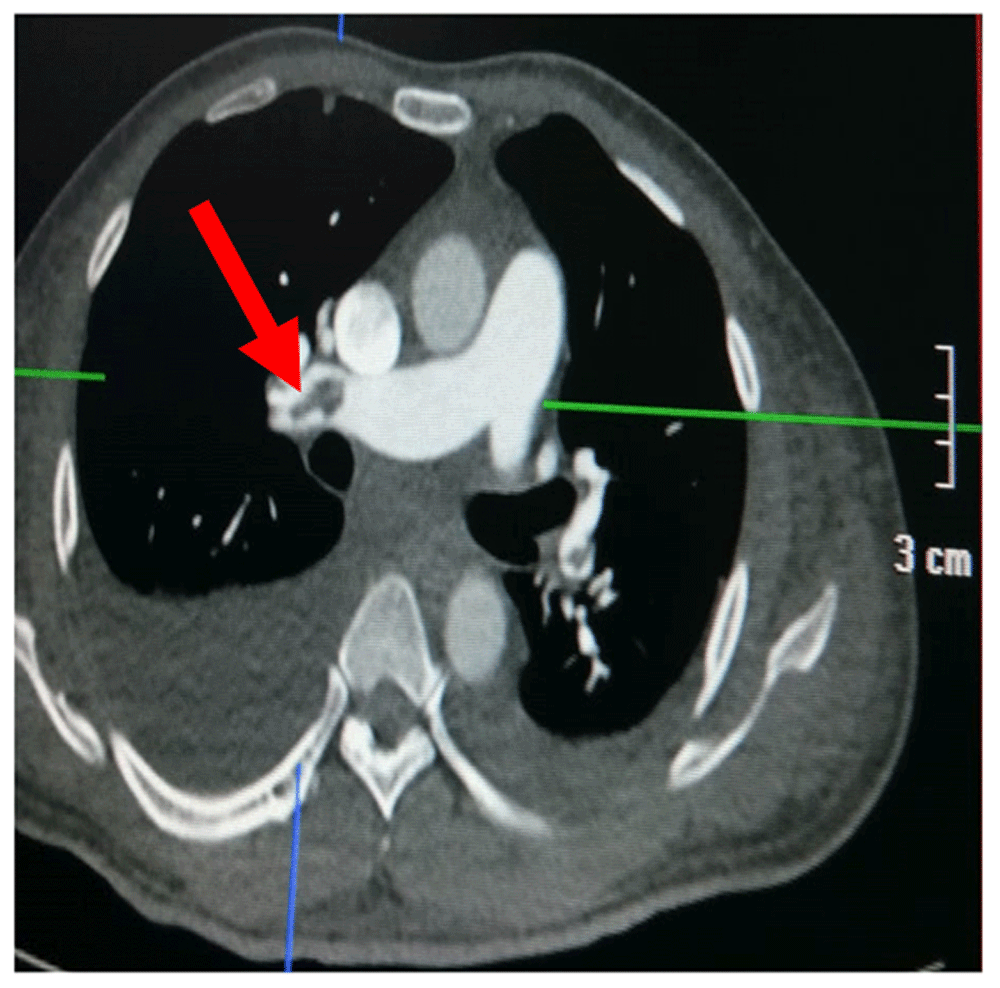

A chest CT scan (Figure 5) showed right pulmonary artery embolism at ± 5.9 cm from bifurcation on the anterior side of the intermediate right bronchus; emboli on the left pulmonary artery bifurcation and the left pulmonary artery basal part; multiple right intraatrial hypodense lesions not showing contrast enhancement leading to a visualization of the right intraatrial thrombus; pulmonary infarction in the lateral-posterior segment of the base of the inferior lobe of the right lung, the lateral-posterior segment of the base of the inferior lobe of the left lung, and the anterior segment of the superior lobe of the left lung; and superior vena cava thrombus at VTH level 1-5. Figure 6 shows the protruded thrombus in the right atrium passing through the tricuspid valve. TTE also showed the position of the thrombus moving from the inferior vena ca va towards the right atrium (Figure 7). The movement of the large protruding thrombus can be seen in supplementary video files 1–35–7.